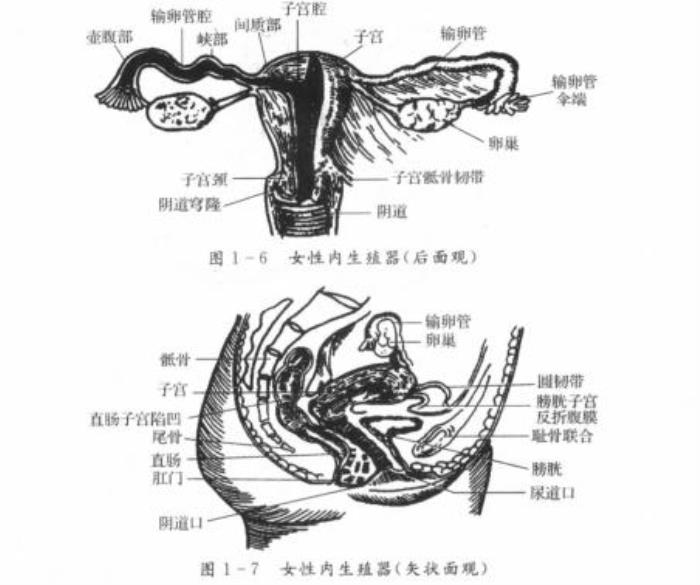

在产科及妇科超声检查中,主要有经腹部B超检查(下文简称腹超)和经阴道B超检查(下文简称阴超)两种方式,它们都可以有效帮助妇产科医生查明患者的盆腔、宫腔及附件区等部位的详细情况。

图1:妇科检查时B超检查的主要部位示意图。图源:邦彦医院学习资料

首先,医生会要求你憋尿,在膀胱充盈时,你才可以接受检查。从上图1我们知道膀胱在子宫的下方,做腹超前憋尿让膀胱充盈,可以使含有气体和内容物的肠道向四周推移,使超声束能以尿液充盈的膀胱作为透声窗,达到清晰显示子宫附件的目的。

阴超的探头是高频探头,扫射角度可达240度,当它被放入检查时(如下图),可以使检查声波更接近被检查的器官,因此能够更加清晰地探测子宫、卵巢的细小血流情况,更利于盆腔器官细小病变的诊断。比如辅助诊断子宫内膜增生、子宫肌瘤、卵巢肿瘤、阴道肿瘤、早期妊娠等妇科和产科常见症状。

图源:妇产科超声诊断